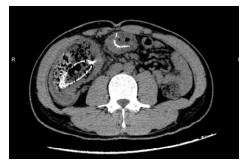

病例3,患者男,33岁。2019年7月6日因“上腹部胀痛10余天”来院急诊,拟“肠梗阻”收治入院。入院查体:腹膨隆,上腹部正中压痛,无反跳痛。CT提示:①横结肠局部肠壁增厚伴管腔狭窄,近段肠管梗阻扩张(图 4);②右肝后段低密度影,建议MR增强。肝脏MR增强:①横结肠局部肠壁明显增厚伴强化,考虑横结肠癌;②肝内多发小斑点,转移瘤可能。肠镜检查示:横结肠肿物,取病理活检后,行肠镜下横结肠支架置入术。肠镜病理提示:横结肠印戒细胞癌。3 d后复查腹部平扫CT示原先扩张的肠腔已明显缩小(图 5)。经多学科讨论后认为目前患者急性肠梗阻症状已明显缓解,建议转肿瘤内科先行转化治疗。患者分别于2019年7月19日、8月7日和8月29日共行三次FOLFIRI方案化疗。2019年9月20日复查腹部增强CT示:横结肠癌支架术后,较前相比,局部肠壁增厚明显减轻;右肝低强化结节灶较前缩小。于2019年9月23日转入普外科,术前再次行多学科讨论后,于10月4日行腹腔镜下横结肠癌切除手术(图 6),手术过程顺利。术后病理报告:横结肠印戒细胞癌,T3N1M1。患者术后接受定期规律辅助化疗,目前恢复良好。

| 图 5 放置横结肠支架3 d后复查腹部平扫CT示原先扩张的肠管已明显缩小 |